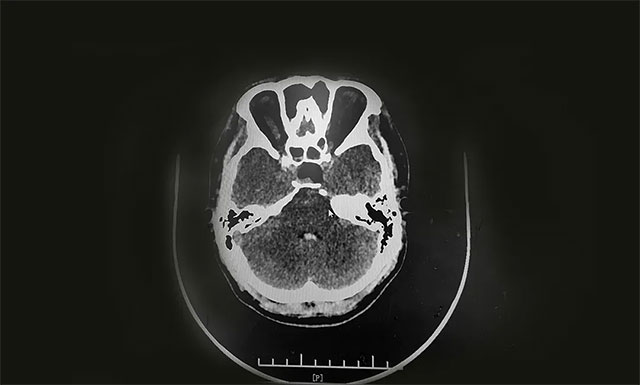

目前,莉莉正在恢复中,经过检查其体内泌乳素、生长激素正逐步恢复正常。李士其教授叮嘱其出院后要做好定期复查。

▲ 术后CT显示肿瘤被切除